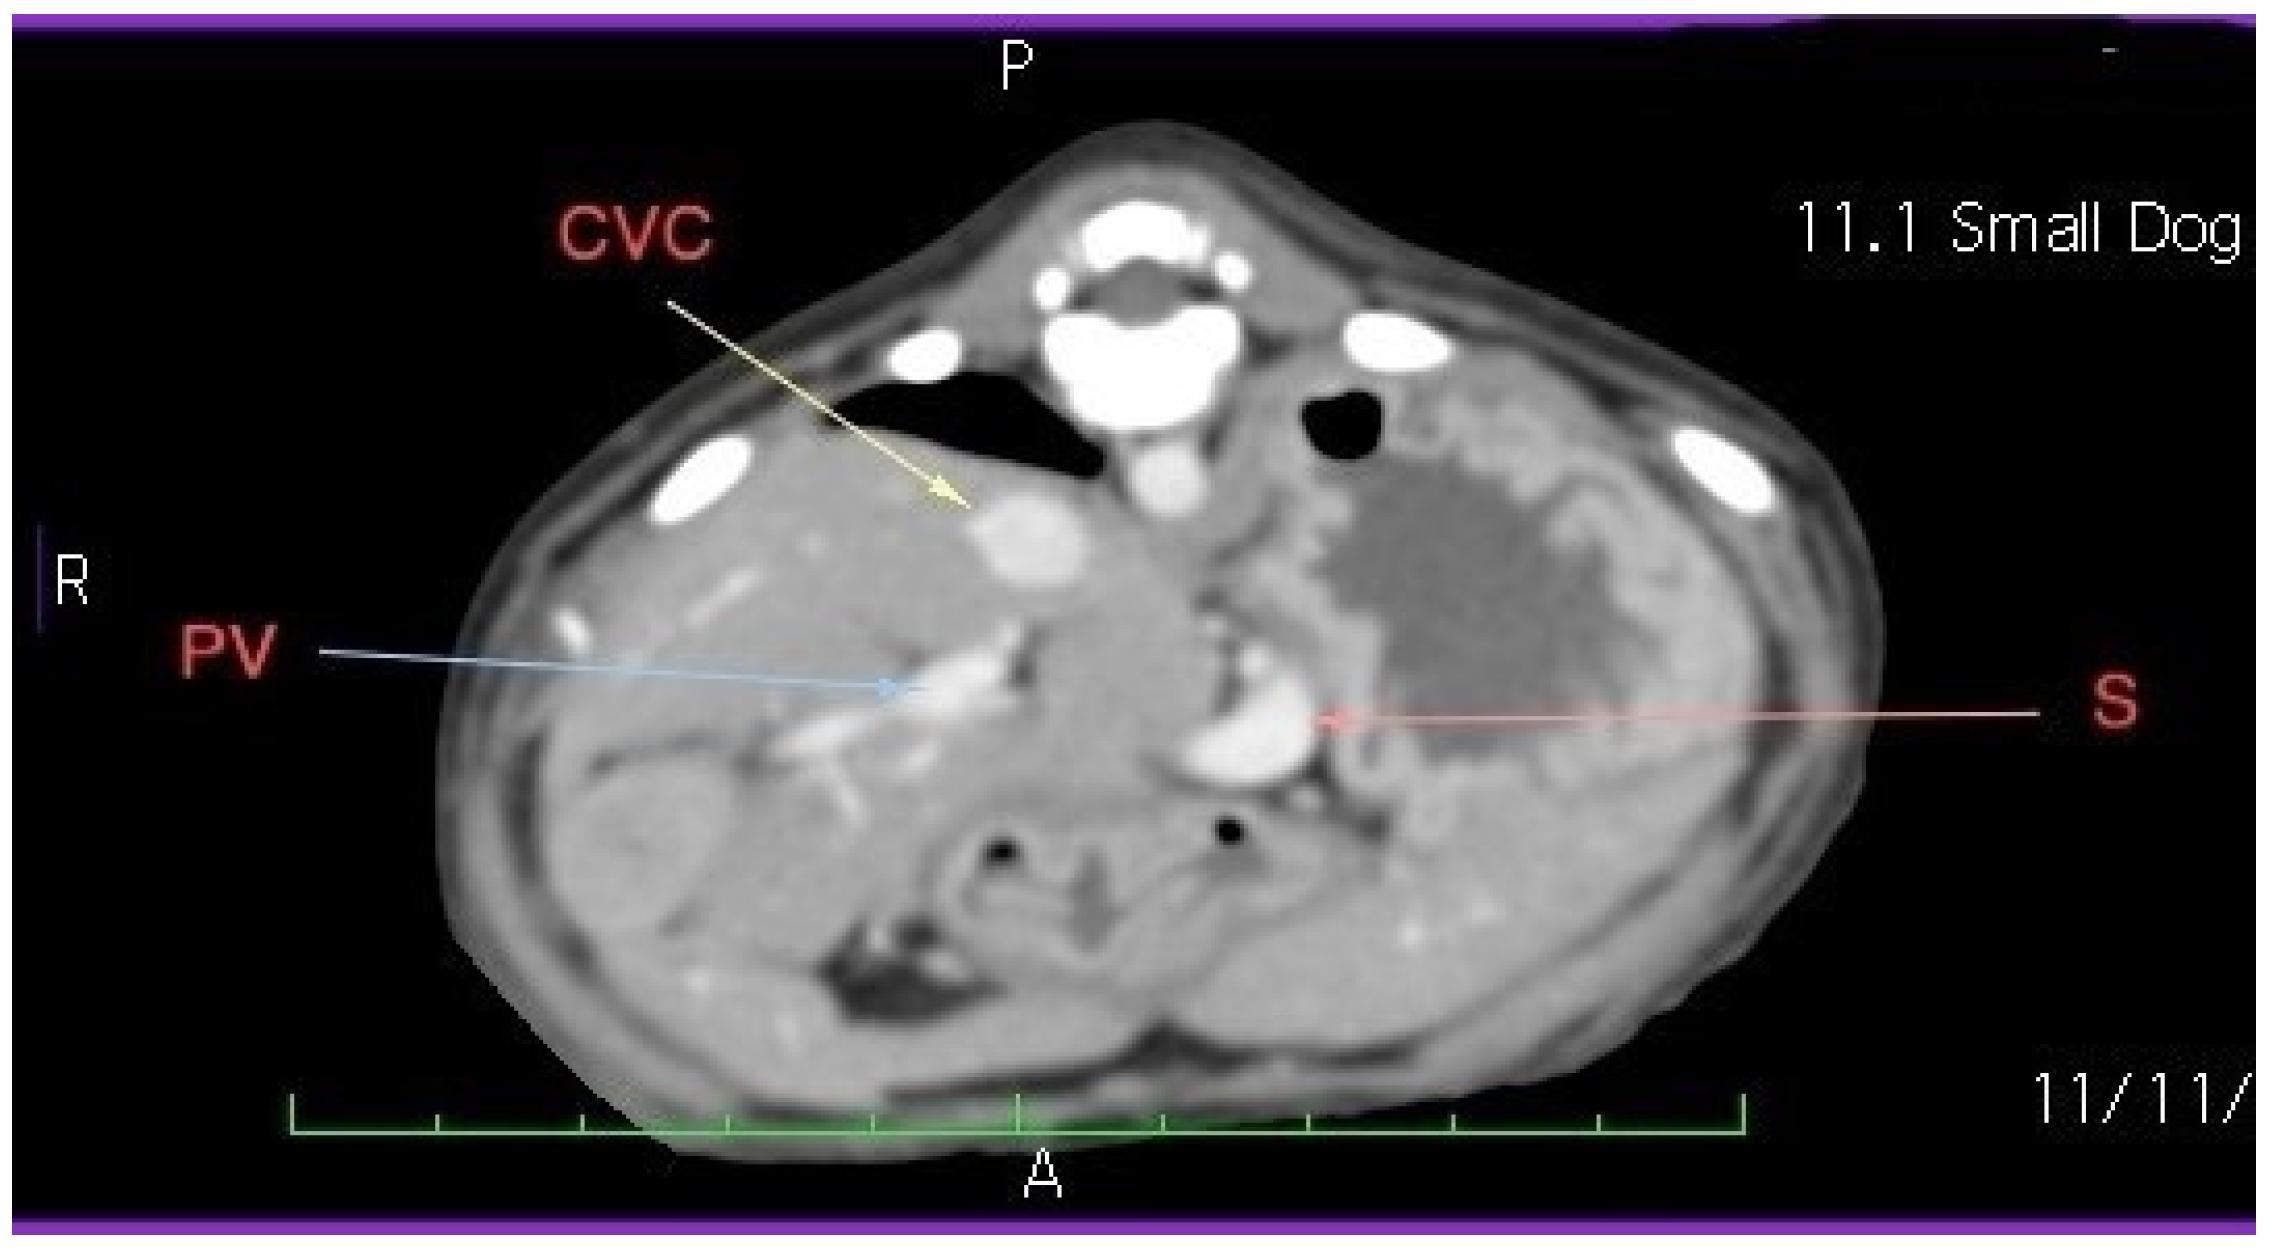

Laboratory tests showed a hemogram with neutrophilic leukocytosis, and serum biochemistry revealed abnormalities in routine hepatic markers, including AST 130 U/L (normal range of 14–45 U/L), ALP 207 (normal range of 20–150 U/L), and GGT 9 (normal range of 0–7 U/L). An abdominal ultrasound examination (My Lab 40 ultrasound machine, Esaote Pie Medical, Maastricht, The Netherlands) revealed a congenital portosystemic shunt (Figure 1) (in comparison to a physiological aspect, Figure S1), for which the patient was recommended to undergo bile acid testing and advanced imaging (abdominal CT). For a rapid diagnosis and due to financial reasons, the owner agreed to advanced imaging, and temporarily declined the bile acid testing. CT examination under chemical restraint (Ketamine, Kepro, Deventer, The Netherlands, at 0.1 mg/kg IV and medetomidine, Domitor, Orion Pharma, at 0.05 mg/kg IV) revealed a large extrahepatic porto-caval shunt (Figure 2) associated with multiple conical cortical brain lesions that were hypodense, with reduced or absent contrast uptake, along with more extensive biconvex lesions, including along the cerebral sulci (Figure 3). A final diagnosis of portosystemic shunt and presumed hepatic encephalopathy was established.

Figure 2. Abdominal CT exam. Large extrahepatic portocaval shunt, Bichon dog, 3 months. Following the caudal vena cava (CVC) from the caudocranial direction, it is observed that it runs parallel to the portal vein to the prerenal level (cranial to the kidneys), where it gives a ventral branch that descends ventro-laterally to the left, follows the small curvature of the stomach, then turns to the right and joins the portal vein (PV) at the level of the hepatic hilum.